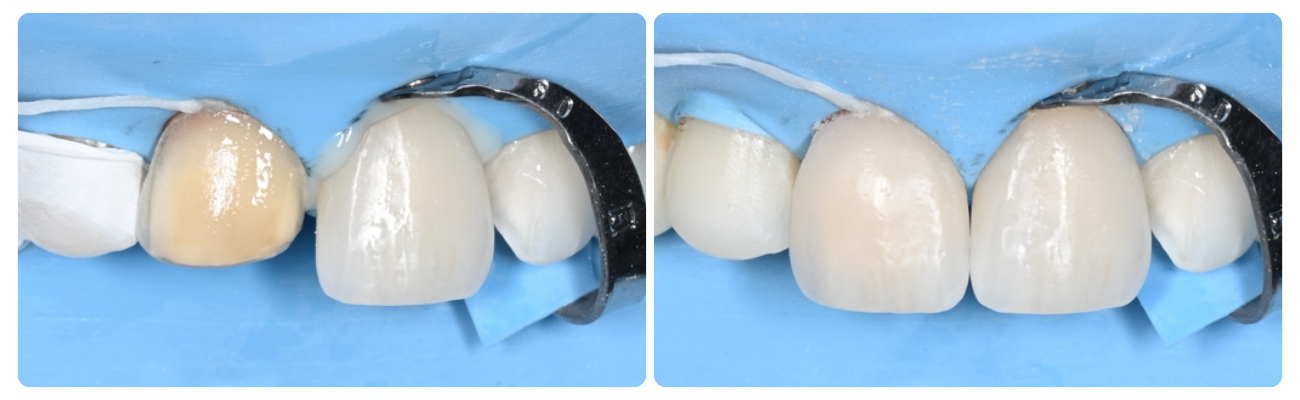

D E F I N I T I E V E   P L A A T S I N G   V A N

K E R A M I S C H E   R E S T A U R A T I E S

We hebben een zeer grondig proces voor de plaatsing van de definitieve keramische restauraties. Deze stap wordt uitgevoerd onder rubberdam-isolatie (tenzij gecontra-indiceerd) om maximale hechtsterkte te bereiken en een schone omgeving te creëren voor de bonding-stappen. De meeste van onze tandheelkundige procedures worden uitgevoerd onder rubberdam-isolatie — de voordelen zijn talrijk. Vraag ons waarom tijdens uw volgende bezoek!

Definitieve Plaatsing - Keramische Restauraties